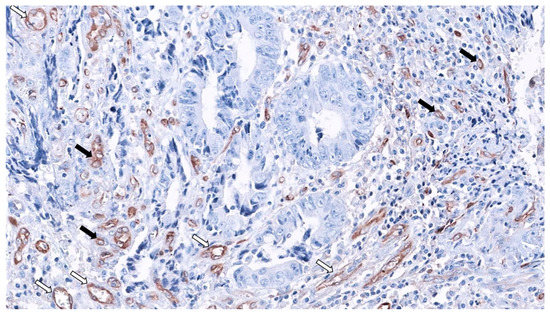

Figure 3.

Fascin1 expression in SAC-staining tumor-budding cells (black arrows) and abundant surrounding microvessels (white arrows) 20× original magnification. (Source: Authors).

MVD was significantly higher in SACs, and, surprisingly, serrated morphology was the only significant predictor of MVD in CRC after multivariate analysis. Finally, regarding the mechanism of HIF-1α stabilization, HIF-1α expression was characteristic of well-vascularized tumor in SACs, suggesting a hypoxia-independent mechanism. Besides, in this study, neither BRAF nor KRAS mutation status was associated with HIF-1α and VEGF expressions, nor with HIF-1α stabilization in CC or SACs. Even more, the great majority of SACs carrying wild-type alleles for KRAS and BRAF (81%) were HIF-1α proficient, pointing out to other mechanisms for HIF-1α stabilization in SACs [25]. Figure 3 shows the abundance of SAC-associated MVD using fascin1 immunohistochemistry.

Fascin1 emerged as an immunohistochemical marker for SAC diagnosis, as the positive expression of fascin1 was observed in 88.6% of SACs and in 14.3% of CCs (88.6% sensitivity, 85.7% specificity) [12]. Intriguingly, Tao et al. had previously observed that β-catenin is associated with the actin-bundling protein fascin in a non-cadherin complex. In fact, these authors observed that fascin1 and E-cadherin use a similar binding site within beta-catenin and that fascin and beta-catenin co-localize at cell–cell boundaries and dynamic cell-leading edges of epithelial and endothelial cells [111], thus giving an explanation of why β-catenin was not observed in the nuclear location in SACs. Fascin1 protein localizes to the core actin bundles forming spikes and filopodia at the leading edge of migratory cells, increasing migration in several cell types [112] and therefore, it has been associated with adverse prognosis in CRC [113]. These facts can partly explain the higher incidence of adverse prognostic histologic factors at the invasive front of SAC (HG-TB and weak peritumoral lymphocytic infiltration (PLI)) and the worse outcomes observed in SACs [18]. Additionally, fascin1 expression is associated with shorter survival, as has been reported previously in CRC [114], thus supporting earlier observations showing that SAC fares worse than CC [113]. Induced expression of fascin1 in colorectal cancer cells increased migration and invasion in cell cultures and caused cell dissemination and metastasis [115]. Figure 3 shows the expression of fascin1 in both blood vessels and SAC cells at the invasive front, creating tumor budding.